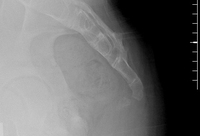

Dynamic lateral sacrococcygeal x-ray in a patient with chronic idiopathic coccygodynia, showing 30° of anterior flexion while sitting

From the personal collection of Dr R. Schrot